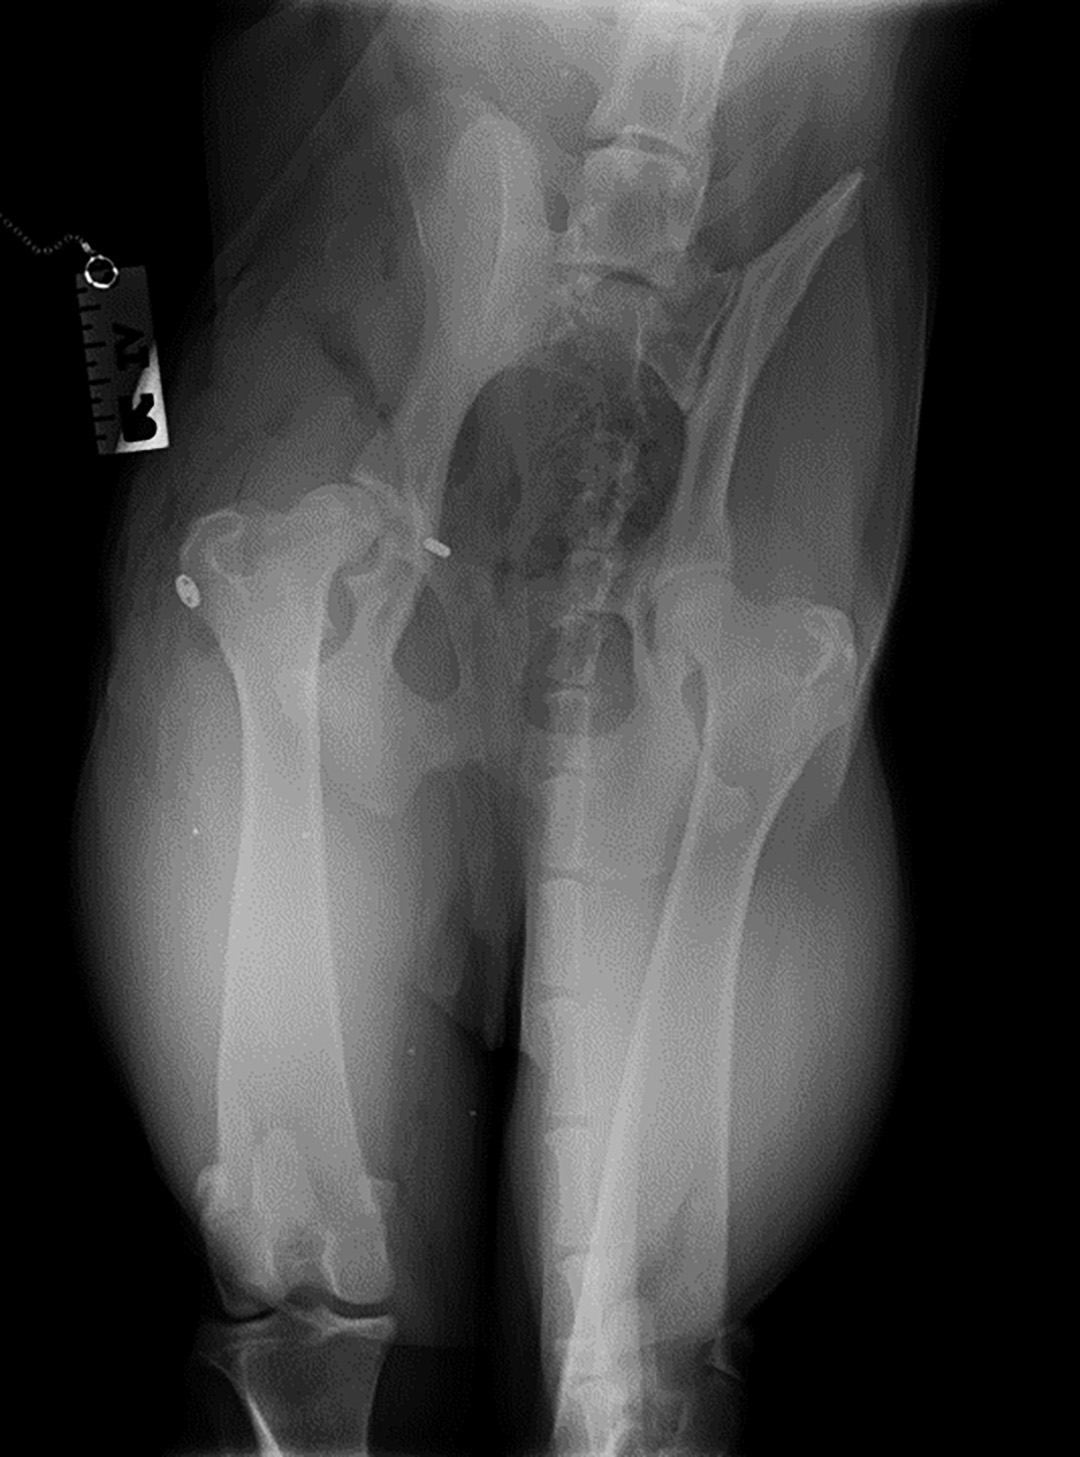

Radiographs were taken to confirm the presumptive diagnosis of hip luxation.

On review of his radiograph, cranial dorsal hip luxation was confirmed. Abnormalities such as hip dysplasia, avascular necrosis of the femoral head (Legg Perthes disease), fractures on the femoral neck, head and great trochanter were ruled out.

Figure 2  Dorsoventral radiograph showing cranial dorsal luxation on the right side